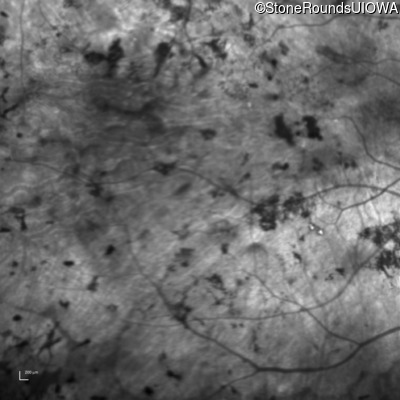

Infrared Fundus Photograph - Right - Light Perception

Exemplar

Infrared Fundus Photograph - Left - Light Perception